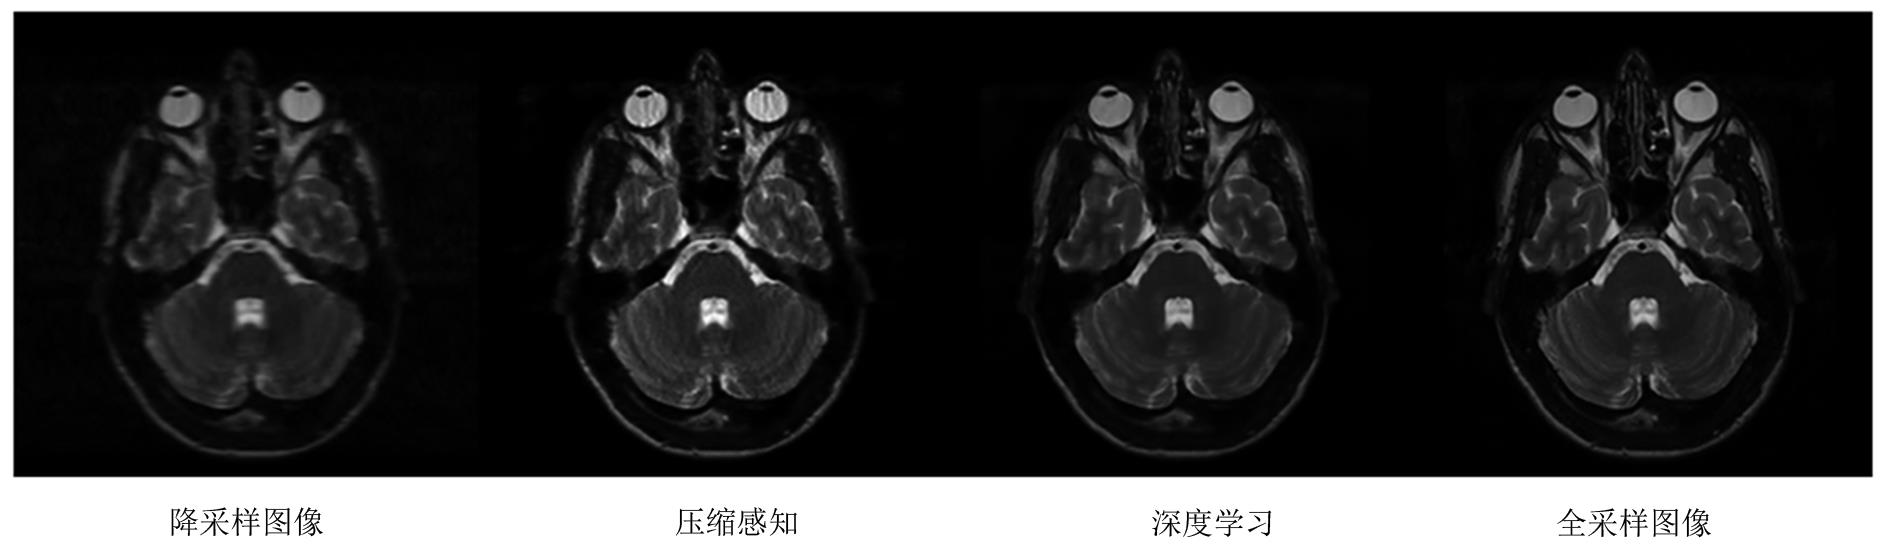

近年来,基于深度学习的方法被提出并成功应用于MR成像,多种针对降采样图像重建的算法相继出现。以大数据作为先验知识,以其更快速的前馈网络处理速度和更好的重建效果,逐渐成为MR重建算法的研究新热点。降采样的MR重建算法经历了半扫描直接重建、基于CS和低秩等方法的传统算法,到基于深度学习的新兴算法(图1),其重建速度逐渐加快,重建效果去伪影、降噪等方面逐渐加强,可适用的降采倍数也逐步提高。以颅脑T2WI为例(图2),在4倍降采样下使用不同类型算法的重建效果,直接重建的图像受到严重的伪影影响,组织结构难以辨认;使用CS的传统算法重建对噪声和伪影有一定的去除作用,但图像质量仍然不佳;使用深度学习算法重建的图像较好地抑制了降采伪影,还原了全采样图像中的解剖结构信息。基于深度学习的MR重建算法将进一步推动医学影像成像速度和质量的提高。